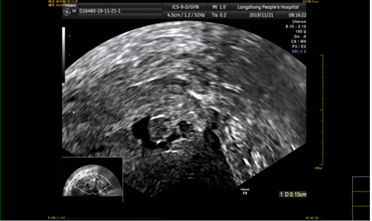

该患者孕囊位于子宫切口处肌壁内,且该处肌层菲薄,厚约3.75px(如图1,2,3)。出血风险及子宫穿孔风险极大。为了保留生育功能,确保患者生命安全,我院妇科积极发起多学科联合诊疗(MDT)会议,特邀请放射科、麻醉科、超声科等相关科室开展讨论,一致决定先由放射科行子宫动脉栓塞术并灌注甲氨蝶呤杀胚治疗(微创介入),72小时之内再行清宫术。最终,该患者在放射科顺利完成甲氨蝶呤灌注和双侧子宫动脉栓塞(如图4-5)的情况下,第二天由妇科在超声科床旁监护下成功完成清宫术(如图6),宫腔镜检查宫腔及切口处无异常。术中出血仅有5ml(出血量较常规清宫术明显减少),并于术后第三天康复出院。

图2:切口妊娠-孕囊大小

image.png

图3:切口妊娠-孕囊血流图像